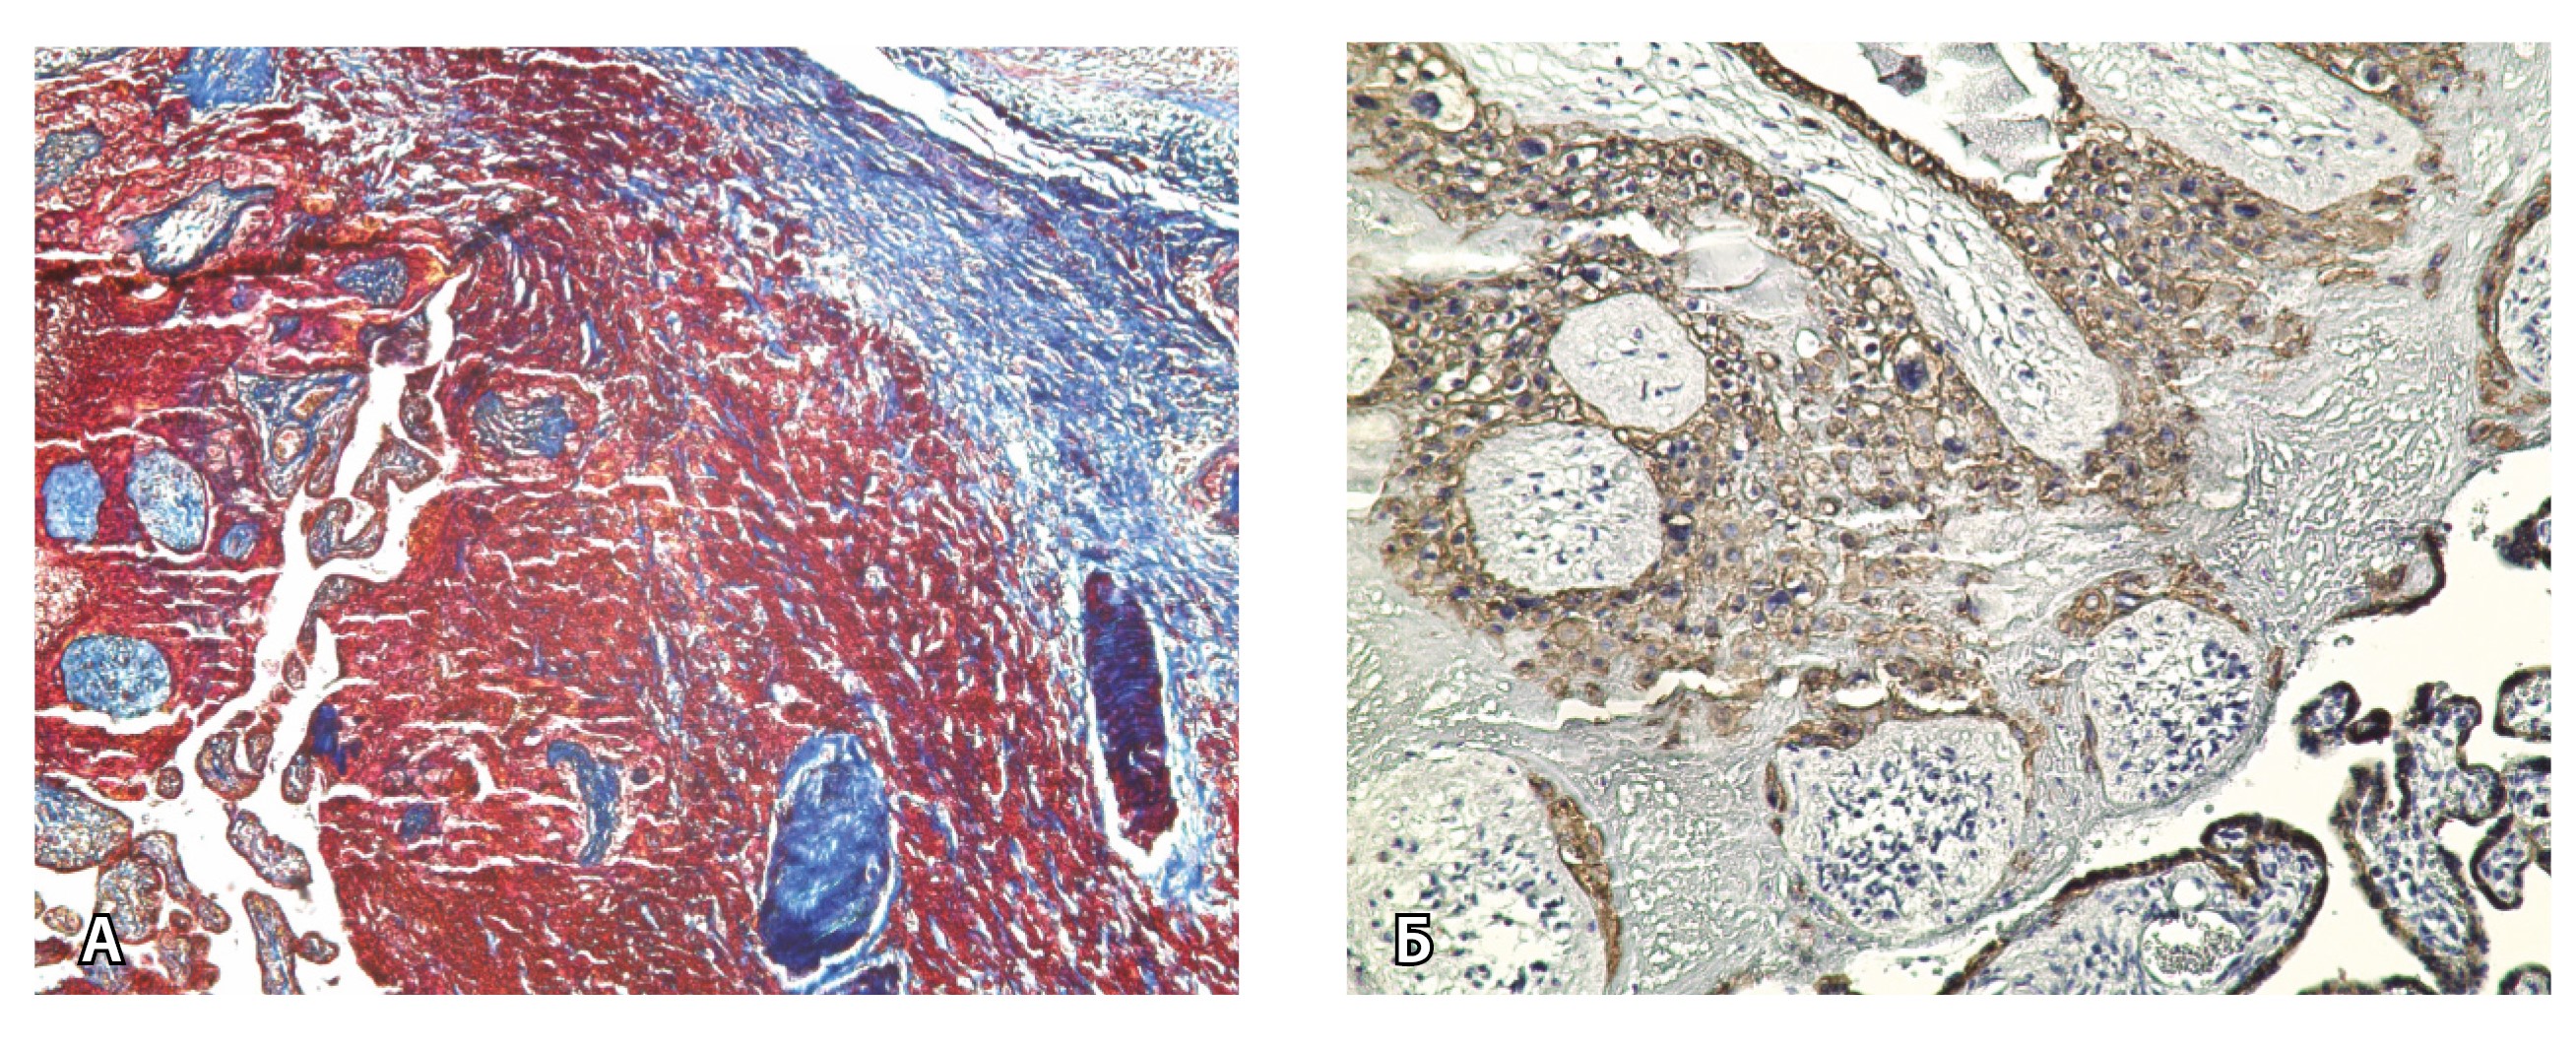

Рис. 5. Сосуды 2-го типа при гиперваскуляризации стенки матки при патологической инвазии: А – организованная ретрохориальная гематома в маточно-плацентарной области, в ее составе много инволютивных якорных ворсин (окраска по Маллори; × 100); Б – в составе гематомы видна пролиферация цитотрофобласта (иммуногистохимическое исследование, маркер цитокератин 8; × 100)

При pl. increta наличие патологических сосудов на изображениях МРТ связано с неполной гестационной перестройкой радиальных артерий, расположенных в срединном слое миометрия. Так, при окраске по Маллори они определяются как сжатые комплексы артерий среднего калибра, с частичным замещением внутренних слоев стенки матки, темно-красными фрагментами плодного фибриноида. На серийных срезах видно, что в этой артерии присутствует достаточное количество инвазивного цитотрофобласта (маркер цитокератин 8), но предыдущий срез подтверждает замещение мышечной оболочки фиброзной тканью как в стенке радиальной артерии, так и в периартериальном пространстве (рис. 8).

Рис. 8. Сосуды 3-го типа при гиперваскуляризации стенки матки при патологической инвазии. Внутриматочная гиперваскуляризация с дефицитом толщины миометрия, наличием рубцовой ткани, недостаточная гестационная перестройка радиальных артерий (аналог pl. increta, PAS 2 по FIGO). А – неполная гестационная перестройка радиальной артерии в составе миометрия (окраска по Маллори; × 50); в верхней части просвета артерии виден слой фибриноида, замещающего эндотелий, такой же фрагмент – в нижней части артерии (стрелка); Б – серийный срез той же радиальной артерии с визуализацией инвазирующего цитотрофобласта (маркер цитокератин 8; × 50); В – серийный срез той же радиальной артерии, при окраске на выявление эластических волокон видна полная дезорганизация эластического каркаса вместо нормальных внутренней и внешней эластических мембран, результат действия инвазирующего цитотрофобласта (окраска по Вейгерту; × 50)